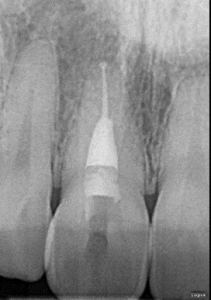

Clinical Cases